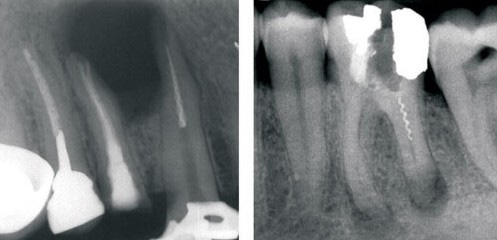

Мануальная техника — метод первого выбора. Особенно когда канал имеет эллиптическую форму, а под микроскопом видно, что отломок легкодоступен.

Для извлечения отломка нужен удобный доступ к устью канала. Для этого устье расширяется эндофайлами вплоть до верхушки сломанного инструмента. Обычно в качестве эндофайлов используются ручные файлы Hedstroem или их аналоги.

Спиралевидные режущие грани и неагрессивный кончик рабочей части файлов аккуратно расширяют и сглаживают стенки канала. Основная задача такой манипуляции — расширить канал и обойти отломок так, чтобы его можно было расшатать и удалить. В процессе обработки канал несколько раз сушится и обрабатывается ЭДТА, а когда отломок инструмента оказывается полностью в зоне видимости, его расшатывают щипцами Штейглица или тонким кровоостанавливающим зажимом. Если ручным инструментом не получается расшатать и извлечь отломок, мануальную технику комбинируют с ультразвуковой.